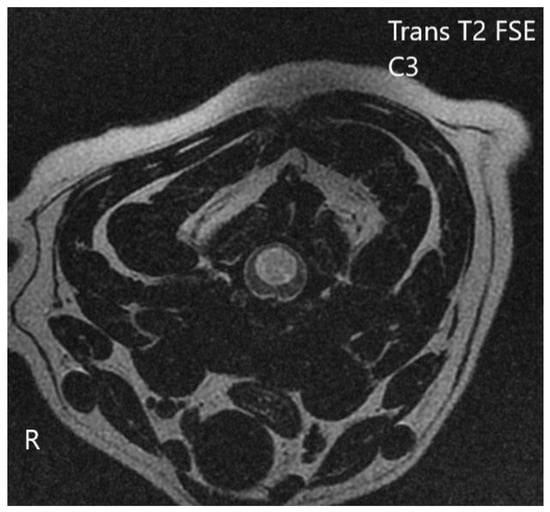

2.1. Imaging Protocols

3.2. Diagnostic Imaging